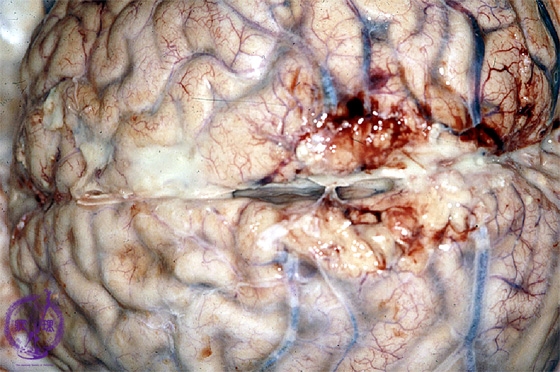

- (3)Purulent meningitis

Macroscopic findings: The arachnoidea was clouded and abscesses were also identified(arrows).